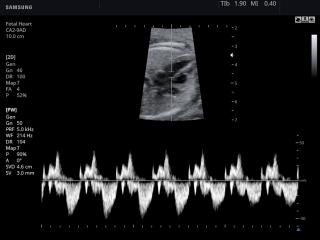

В разделе "Акушерство" атласа представлены результаты ультразвуковых исследований беременных на разных сроках. Здесь вы можете посмотреть изображения внутренних органов, мозга, сердца и пола плода, эхограммы многоплодной беременности, кровотока в плаценте и пуповине, пороков развития и др.